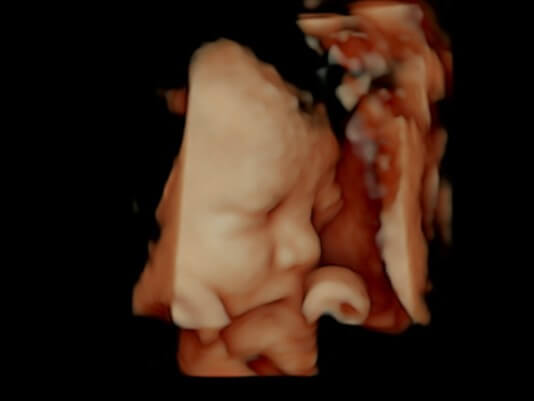

There are few things in this world as precious as the bond between mother and child. Love View was born from the joy of providing a unique prenatal bonding experience for expectant mothers and their family.

SEE OUR WORKWe are a locally owned and operated family business. Our supervising sonographer Samantha is a registered sonographer with the American Registry for Diagnostic Medical Sonography and has over 15 years of experience. She is the mother of four amazing children and loves the opportunity to talk to and support new moms. Our studio has a Board Certified Obstetrician who serves as our Medical Advisor. You can be sure you are in the best hands with Love View.

Pregnancy is an extraordinary time in a woman’s life, we consider it a genuine honor to provide this unique experience to expectant mothers, their family and friends. We look forward to your session. We can’t wait to meet the newest member of your family!